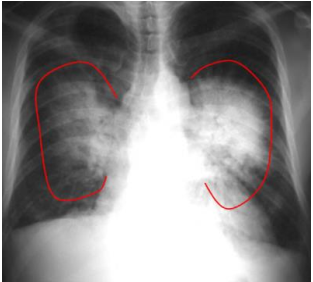

Observe a radiografia, abaixo:

Fonte: https://dapi.com.br/wp-content/uploads/2018/11/bases-radiologicas-das-doencas-toracicas.pdf

Acima, temos uma radiografia frontal de paciente portador de insuficiência cardíaca congestiva. Observa-se aumento da área cardíaca e consolidações bilaterais com padrão de “asa de borboleta”, que indica: